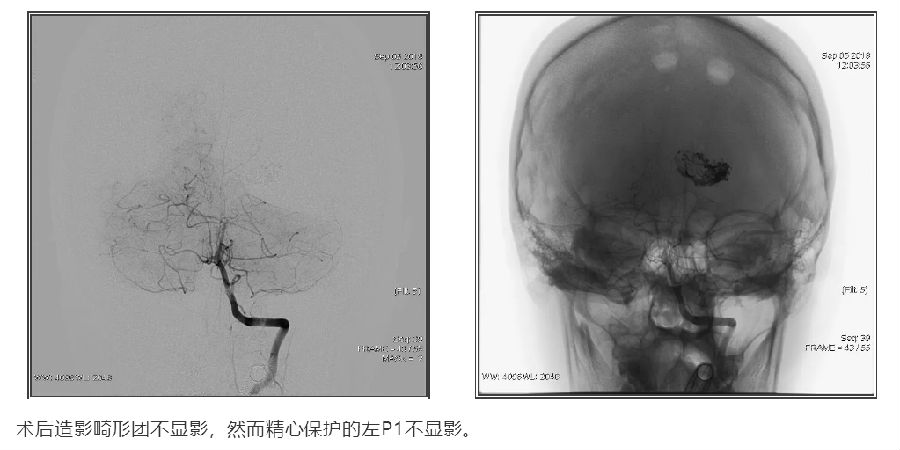

影像融合技术在脑脊髓血管病中探索及创新